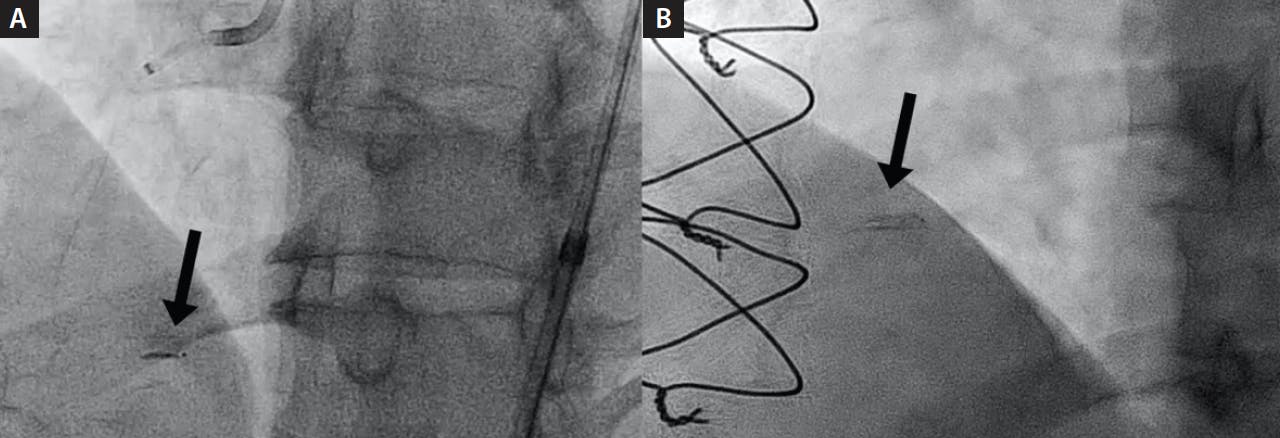

5. Adjust the angle of visualization until the Stingray system is visualized optimally as a straight line (Figure 1).

Figure 1. Optimal Stingray LP orientation: the device appears as a single line with two exit ports (one exiting up and the other down) (A). Least optimal Stingray orientation: the device is en face with the exit ports pointing toward or away and thus it is impossible to decipher their relation to the vessel lumen (B).